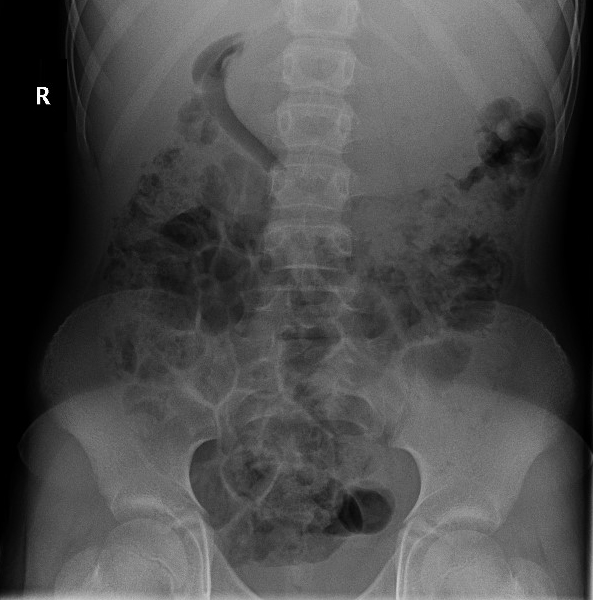

Se realiza una analítica de sangre que resulta normal (hemograma sin alteraciones, bioquímica con función hepatorrenal normal, proteína C reactiva de 2,4 mg/l). Además, se realiza una ecografía y radiografía de abdomen.